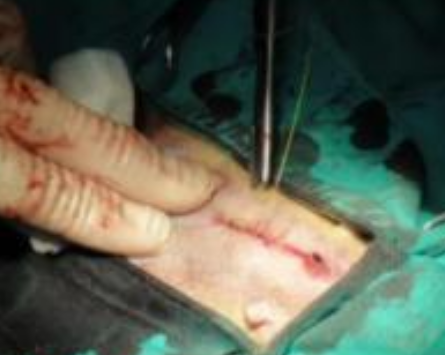

6,皮肤溃烂:骨癌患者患部皮肤可发生溃烂.

手指溃烂

伤口溃烂